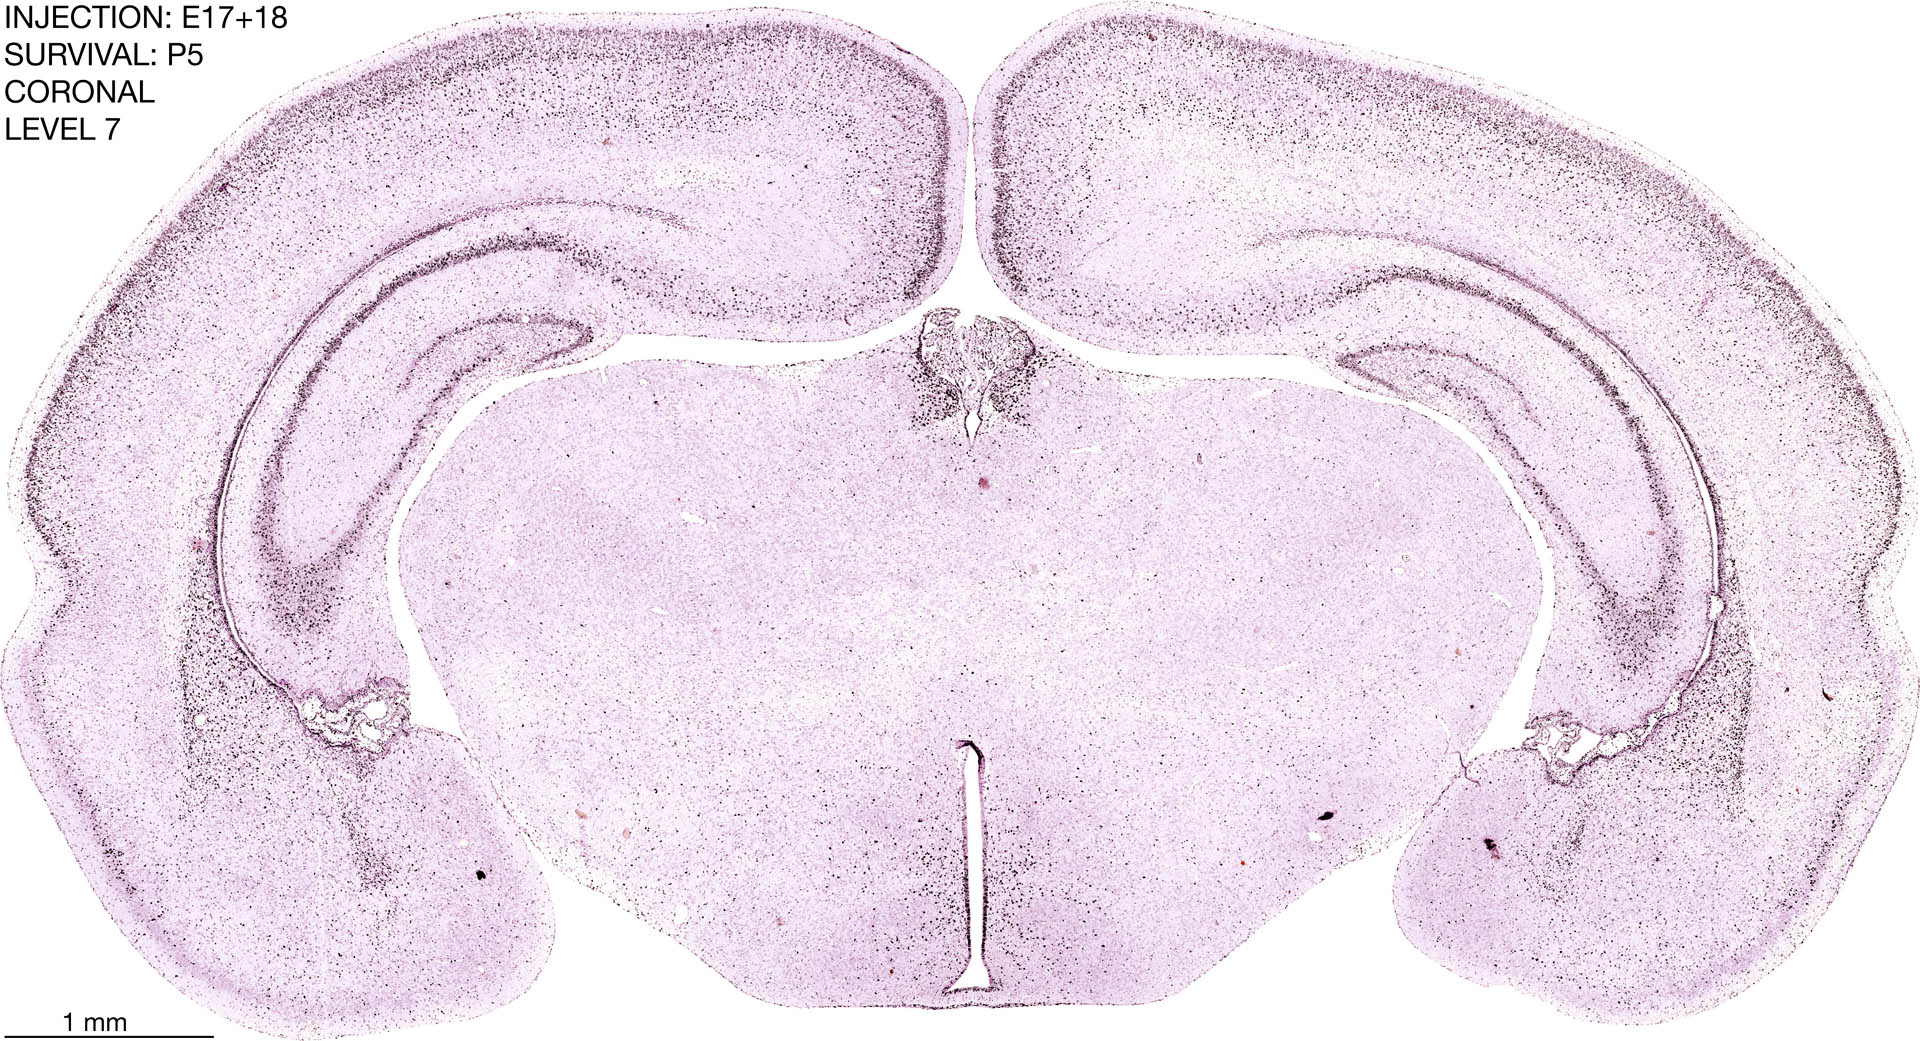

E17+18 P5 Survival The images below are from the brain of a rat that was exposed to tritiated thymidine on E17+18 and survived to P5. Download: Large | High Res Download: Large | High Res Download: Large | High Res Download: Large | High Res Download: Large | High Res Download: Large | High Res Download: Large | High Res Download: Large | High Res Download: Large | High Res Download: Large | High Res Download: Large | High Res Download: Large | High Res Download: Large | High Res Download: Large | High Res Download: Large | High Res Download: Large | High Res Download: Large | High Res Download: Large | High Res Download: Large | High Res Download: Large | High Res Download: Large | High Res Download: Large | High Res Download: Large | High Res Download: Large | High Res Download: Large | High Res Download: Large | High Res